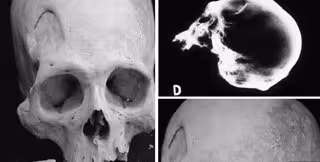

Foto: INTERNATIONAL JOURNAL OF OSTEOARCHAEOLOGY

Los expertos explican que los esqueletos de la región han puesto de manifiesto la violencia que protagonizaba esta población: como huesos rotos o cráneos con agujeros. Pero también se pueden ver marcas que sugieren que esta antigua cultura realizaba cirugía craneal en un intento por salvar vidas.

Los cráneos incluso revelan pistas sobre cómo estas técnicas rudimentarias evolucionaron con el tiempo hasta tener una mayor tasa de éxito.

El equipo se centró en la práctica de la trepanación en la región a partir de cráneos recogidos en yacimientos de la zona del Titicaca. Esta práctica es una antigua forma de cirugía craneal, que fue utilizada para fines médicos y rituales. En ese momento había varios tipos de trepanación: raspado de cráneo, cortes lineales y ranura circular.

Estudios elaborados sobre momias peruanas insinúan que se usaban herramientas de metal en los procedimientos y se colocaban placas sobre el agujero después, aunque, según los expertos, no se han encontrado evidencias de estos sucesos en los nuevos cráneos.